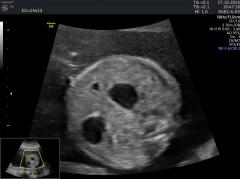

Se presenta el caso de una paciente de 39 años de edad, primigesta, sin antecedentes personales ni familiares de relevancia. La paciente adjunta el estudio de screening de aneuploidías de la semana 11-14, que arroja bajo riesgo.

Las imágenes que se presentan a continuación corresponden al estudio morfológico fetal realizado en la semana 24.

Seleccione la opción correcta :

A. Se visualiza cámara gástrica dilatada, conectada con una imagen quística anecogénica, de probable origen duodenal (Signo de la doble burbuja).

B. La anatomía es de apariencia normal para la edad gestacional.

C. Los hallazgos podrían corresponder a una probable atresia esofágica.

D. Los hallazgos podrían corresponder a una dilatación quística del conducto biliar.